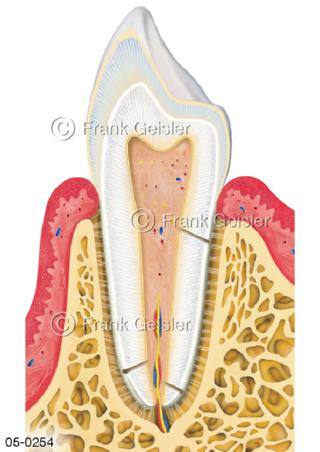

Bildergalerie Skelettsystem

Bilder zum Skelettsystem zeigen die Stützstruktur des menschlichen Körpers, die Knochen, eine besonders harte Form des Bindegewebes und Stützgewebes, welche das menschliche Skelett bildet, die Knochen des Stammes, der Extremitäten sowie der Gelenke